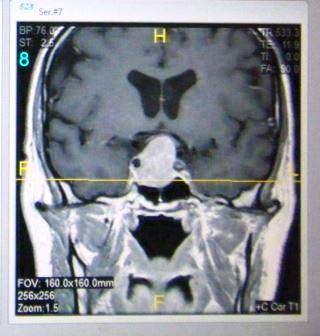

Two years later, I was diagnosed a pituitary tumor. It is a prolactinoma, causing excess production of the hormone prolactin, which promotes milk production in women. I was successfully treated with drugs to shrink the tumor to its current size of 5mm. Unfortunately the tumor crushed surrounding cells in my pituitary. In succession, I lost production of testosterone, thyroid hormone and recently cortisol.